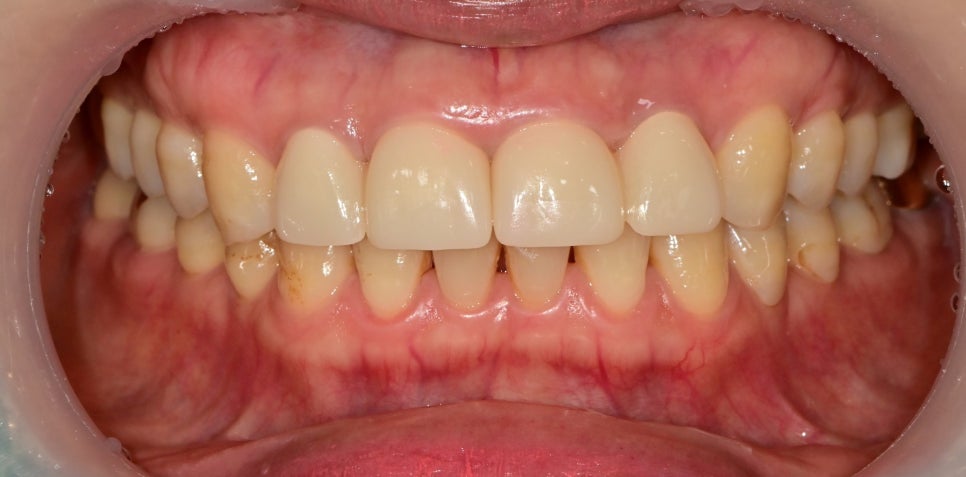

최종 보철물의 형태입니다.

대칭적인 4개의 앞니를 보철치료를 했기 때문에 색상이나 모양을 대칭적으로 만들어주기 용이했습니다.

기존에는 4개 치아를 하나로 묶었지만 이번 치료에서는 2개씩 묶어 진행했습니다.

치아를 하나씩 나눠서 보철을 씌워주는 것이 가장 좋지만

하나씩 진행하기에는 약한 치아도 있었고, 오랫동안 묶여있던 치아를 하나씩 씌우게 되면

치아의 이동이 생길 수 있기 때문에 여러 사항을 고려했을 때는

2개씩 묶어 해주는 것이 추후 관리, 유지 측면에서 좋다고 판단했습니다.

비율적으로는 치아의 길이가 좋지만

아래 치아와 교합이 간섭되는 부분들이 있어 충분히 조정해 드리고 최종 접착을 했습니다.

아마 교합조정이 까다로워서 과거에 치아를 짧게 제작한 것이 아닌가 추측을 해볼 수 있습니다.

결과적으로 치아의 비율과 색상, 형태 모두 환자분께서 만족해하셔서 보람을 느꼈습니다^^

치아의 비율만 바꿔줬을 뿐인데 훨씬 자연스러운 것을 확인할 수 있습니다.